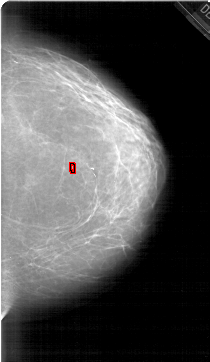

A_1452_1.RIGHT_CC

RIGHT_CC LINES 6511 PIXELS_PER_LINE 3766 BITS_PER_PIXEL 12 RESOLUTION 43.5 OVERLAY

FILE: A_1452_1.RIGHT_CC.OVERLAY

TOTAL_ABNORMALITIES 1

ABNORMALITY 1

LESION_TYPE CALCIFICATION TYPE PLEOMORPHIC DISTRIBUTION CLUSTERED

ASSESSMENT 4

SUBTLETY 4

PATHOLOGY BENIGN

TOTAL_OUTLINES 1

BOUNDARY